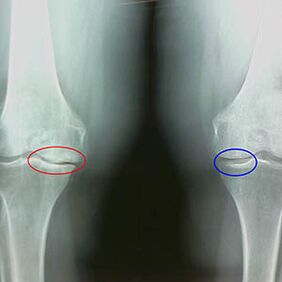

Caratteristiche del raggio X precoce della seconda fase dell'artrosi del ginocchio:

- I bordi appuntiti dei tubercoli interni sulla tibia, a cui è collegata la banda definita a croce;

- Restringimento del divario comune sul lato mediale;

- I bordi appuntiti del condil osseo sui lati mediali, meno spesso sul lato, a seconda dello sviluppo del valgo o della deformazione della connessione variante.

Per la seconda fase di Larsen Il restringimento del divario comune di oltre il 50% è caratteristicoTuttavia, questo può essere controllato solo in dinamica o in confronto a un articolazione ininterrotto.

L'immagine a raggi X mostra la presenza di osteofiti, un cambiamento nello spazio tra le ossa del femore e la tibia, che indica la perdita di cartilagine nel ginocchio. A volte i raggi X delle articolazioni del ginocchio mostrano segni significativi di usura della cartilagine, ma i pazienti non hanno dolore significativo.Al contrario, l'artrosi del primo stadio può disturbare la funzione del ginocchioLa causa del dolore sono i muscoli ipotonici.